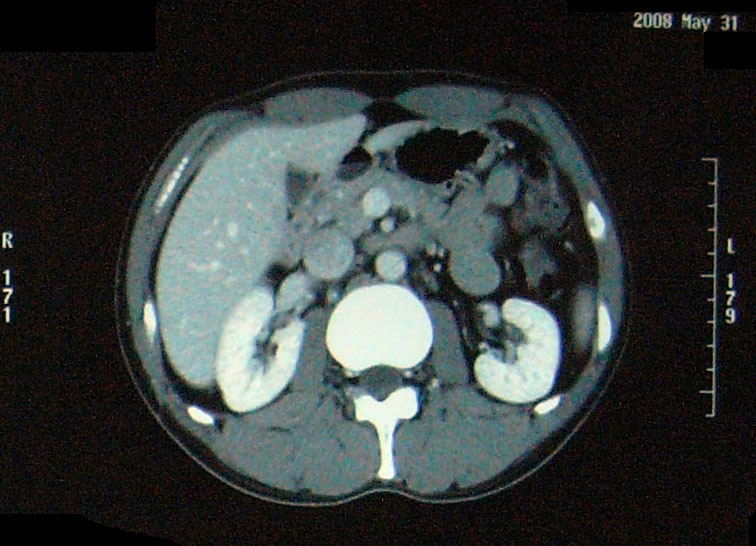

問題なし 【腫瘍マーカー】 HCGβ:<0.1 問題なし 【中性脂肪】 219→137 基準内(38-193)に入った 今回、検査画像をデータでもらってきた。 後腹膜の転移した箇所の前後4枚を2003年から2010年まで並べてみた。 http://gomatsushita.gozaru.jp/ct/album/index.html 2006/7/18の画像を見ると腫瘍がハッキリ見える。 BEP2クール後の9/27の画像では明らかに縮小もしくは消滅。

【CT画像】

単純CT:特に変化を認めず。 【腫瘍マーカー】 HCGβ:<0.1 問題なしでした! 今日は画像はありません。 理由は、病院側でデジタル化が進んでいて、PCモニターでの画像確認となったからです。 今日はフィルムも用意されませんでした・・・・。 先生曰く、そのうちフィルムもなくなるだろうと。 そのときにはCD-R等に焼く対応もするようになっているはずだと。 早くデータで画像がほしい。その時はたくさんアップしますw。 次回は2月です。